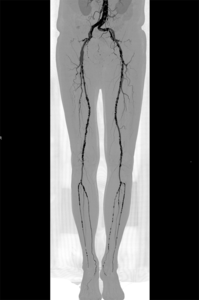

Für die Gefäßuntersuchung steht ein moderner 128-Zeilen-Computertomograf (Siemens Somatom Edge) zur Verfügung. Dieser kann bei einer räumlichen Auflösung von bis zu 0,3 mm kleinste Veränderungen nachweisen. Zur Darstellung der Gefäße wird dazu ein jodhaltiges Kontrastmittel verwendet, welches meist in eine Vene des Armes mit Hilfe einer Spritzenpumpe verabreicht wird. Die Untersuchung selbst dauert weniger als eine Minute.

Aus den dabei gewonnen Schnittbildern sind computergestützte 2D- und 3D-Rekonstruktionen aller Regionen des Gefäßsystemes herstellbar. Dieses Untersuchungsverfahren kommt in unserem Zentrum bei der Diagnostik – Erweiterungen der Bauchschlagader oder andere Gefäße, Durchblutungsstörungen aufgrund von Gefäßeinengungen oder Verschlüssen sowie der Therapieplanung und Therapiekontrolle – zum Einsatz. Einen wichtigen Stellenwert hat die Computertomografie auch bei allen akuten Gefäßerkrankungen und Gefäßverletzungen.